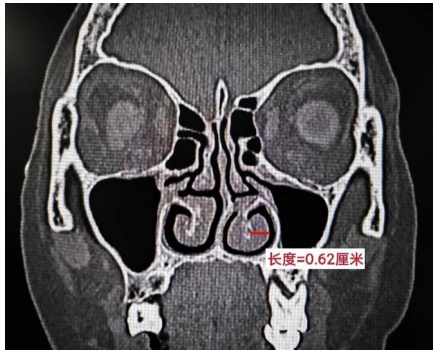

2) 应用美国GE公司64排螺旋CT对患者进行鼻窦平扫并薄层重建,并对患者泪囊、鼻泪管、鼻窦进行完整成像。然后由专业的影像科医生读片、上传结果。在冠状位CT图像上,本研究将鼻中隔超过下鼻甲平面的偏曲归为鼻中隔偏曲,鼻腔内的鼻甲组织显示为明显增厚的软组织区域且厚度>4 mm,归为鼻甲肥厚。见图1。

图 1 鼻中隔偏曲及下鼻甲肥厚

Figure 1 Deviation of nasal septum and inferior turbinate hypertrophy